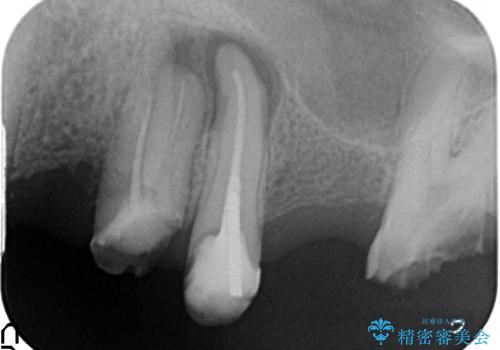

- 歯がない左側でものが咬めず、右側で咬むと歯が痛むので診て欲しいといらっしゃった方の症例です。

根尖病変が認められる歯は再根管治療を行い、歯根が破折していた左上4は抜歯しました。

インプラントは希望されなかったため、左側は1番から7番のロングスパンブリッジによる補綴を行いました。